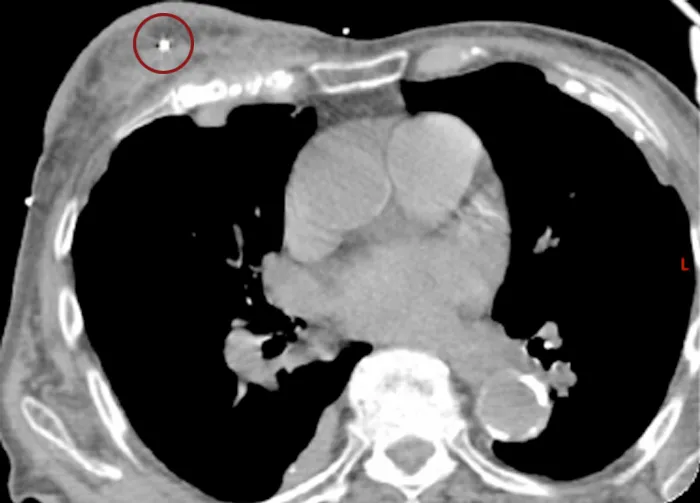

Marker based IGRT is also useful for APBI (Accelerated Partial Breast Irradiation) for example with CyberKnife as shown in the image to the right. .

- Image to the left showing two 0.28×10 mm Gold Anchor markers implanted.